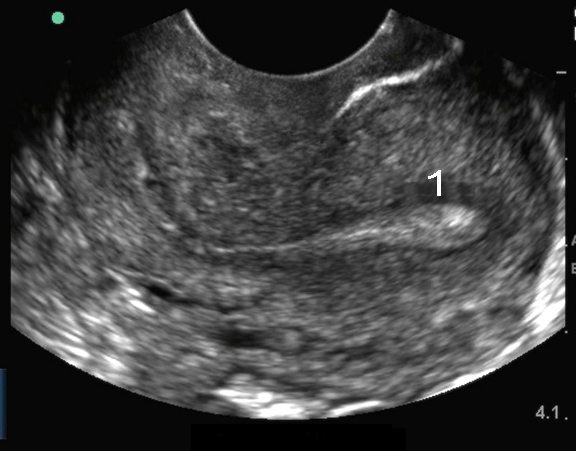

Endovaginaler Ultraschall d. Uterus: Mittellinie, sagittal 2

Retrovertierter Uterus

Endometrium